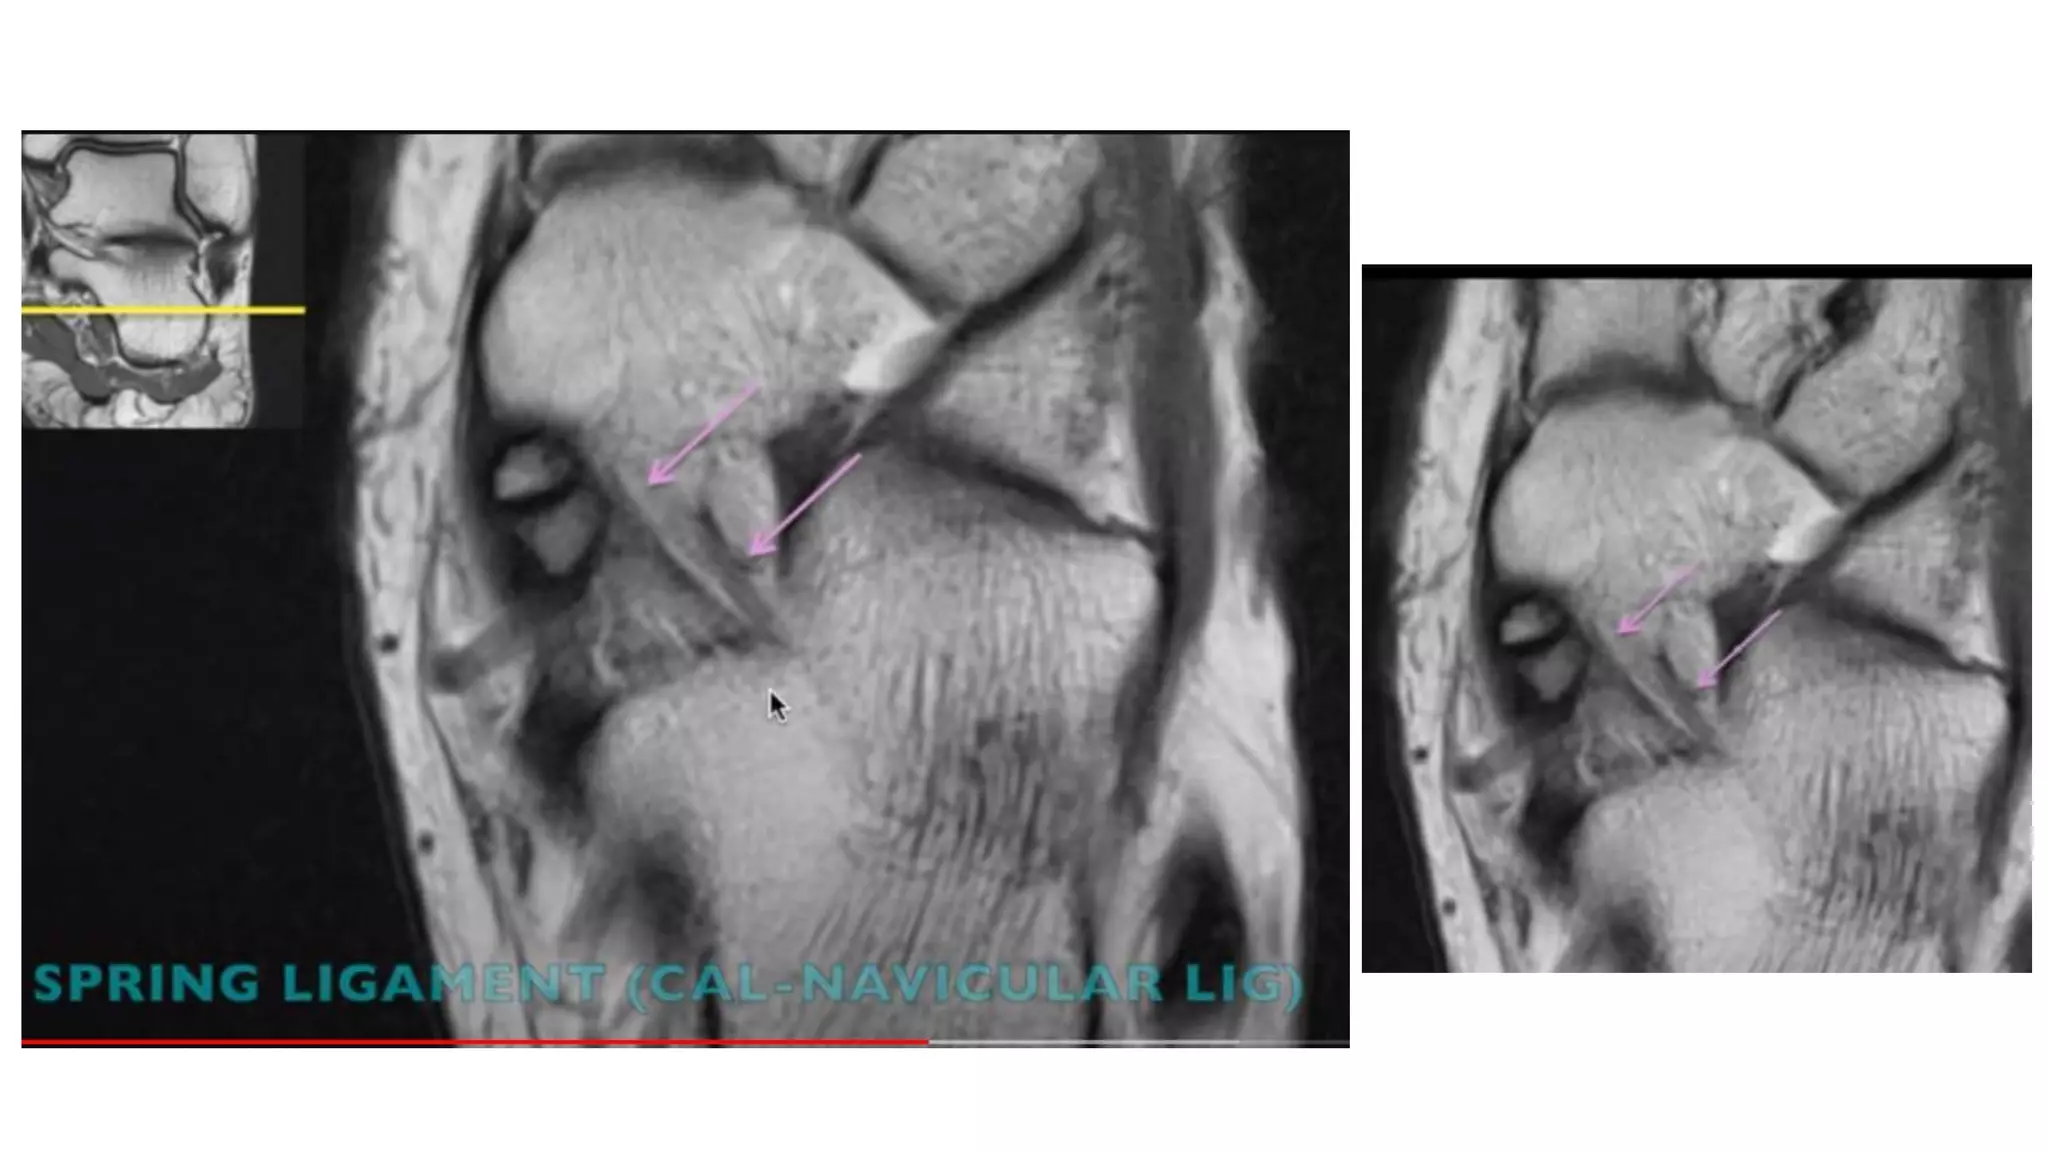

This MRI ankle report describes the anatomy of the ankle, including ligaments such as the anterior and posterior tibiofibular ligaments, syndesmosis ligaments, deltoid ligament, and calcaneofibular ligament. It outlines the tendons in the anterior, lateral, medial, and posterior compartments, including the tibialis posterior, peroneus, flexor hallucis longus, and Achilles tendons. The sinus tarsi is also noted.